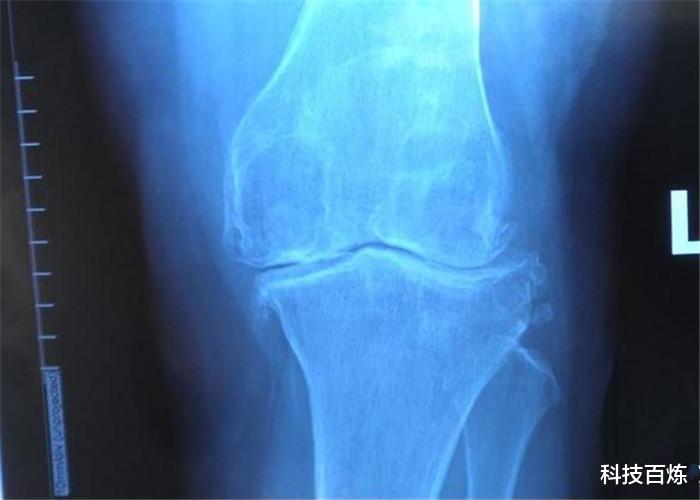

实际上 , 法贝骨就是一种膝盖骨 , 大多会在哺乳动物的身上常见 , 特别是一些灵长类动物 , 比如猴子或者是猩猩 , 只不过这种骨头的作用并不是很大 , 一般都会在灵长类动物身上出现 , 主要就是因为灵长类动物的进化还不完全 , 不过人类是一种高级动物 , 因此 , 法贝骨早就已经被膝盖骨所取代了 。

即便如此 , 现代医学研究表明法贝骨又重新出现了 , 就在上个世纪 , 科学家们研究发现 , 目前全球拥有法贝骨的人已经超过了11% , 按理说这个比例不会再上升了 , 可是到了2019年 , 科学家们又发现这个数字已经涨到了40% 。 假如继续发展下去 , 很有可能在几十年之后 , 全球的人类都会重新拥有法贝骨 。

为什么人类身上又会重新长出法贝骨呢?目前科学家们还无法解释 , 对此有些科学家分析猜测 , 很有可能跟现代人类的运动有关系 , 因为现在越来越多的人开始注意运动 , 所以在这些人的身上才会重新出现法贝骨 , 法贝骨的出现主要是为了增加关节的力量 , 同时也能够避免摩擦劳损 , 同时法贝骨的重新出现 , 如果能够强化人类的关节 , 让腿部有力量 , 那么人类到了晚年之后 , 会不会还可以直立行走呢?对此大家是怎么看待的呢?